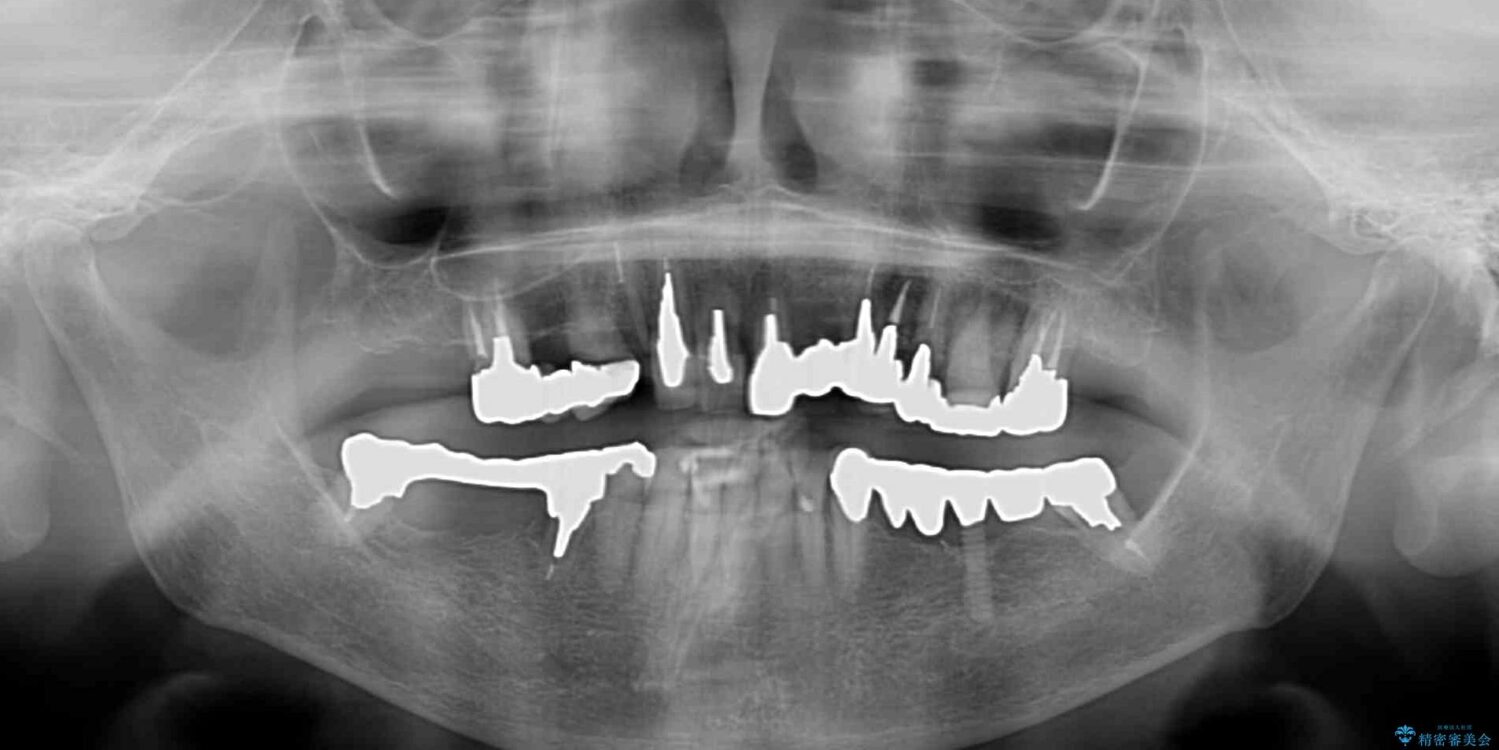

治療計画

上顎犬歯や下顎大臼歯は、必要なところはインプラントを埋入することとしました。

クラウンが不適合であったり、根管治療の必要なほどの痛みのある歯であったり、見た目の気になる前歯などをオールセラミッククラウンに補綴治療を行うこととしました。

治療後について

処置を予定していた歯を仮歯に変えた時点で、下顎前歯の部分矯正を行うかどうかを尋ねたところ、折角なので行いたいと言うことでしたので、矯正治療を行うこととしました。

インプラント埋入や根管治療治療など、治癒に一定の期間を要する処置の合間に矯正治療を行うことで、効率的に治療を進めて行くことができました。